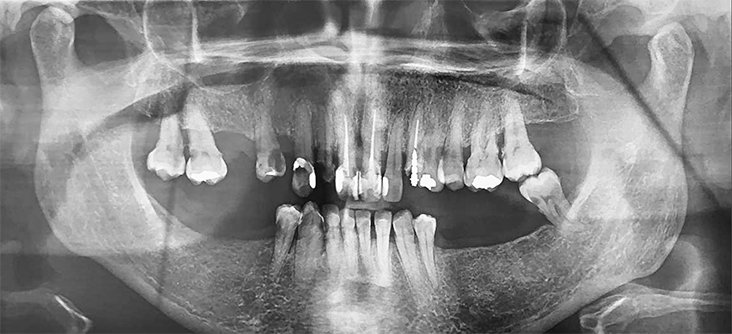

No caso clínico relatado a seguir, é apresentada a reabilitação de uma paciente do gênero feminino, de 45 anos, com o desejo de melhorar o aspecto do seu sorriso. Durante o exame clínico inicial, foi verificada a presença de exposição gengival maxilar excessiva durante o sorriso espontâneo, associada à desalinhamento dentário e presença de restaurações extensas e insatisfatórias nos dentes anterossuperiores (Figuras 1 e 2), além de mobilidade dos dentes 15 ao 25. Ao exame radiográfico, foi observada extensa perda óssea periodontal, além de lesões de cárie/perda de estrutura coronária nos dentes 13 a 23, 15, 24 e 25 (Figura 3), sendo indicada a exodontia desses elementos, seguida da instalação de implantes osseointegráveis.